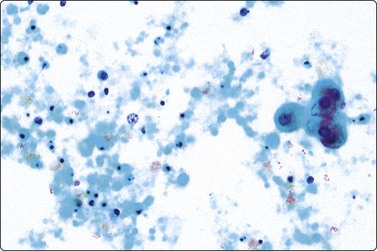

Fat necrosis (Fig. 7.19)

image image image

Fig. 7.19 Fat necrosis

(A) Postoperative fat necrosis. Necrotic tissue, debris and macrophages; fragment of adipose tissue upper right (MGG IP); (B) Fragments consisting of altered adipocytes, macrophages and fat droplets (MGG, IP); (C) Several multinucleated histiocytes with foamy cytoplasm (MGG, HP).

Criteria for diagnosis

A ‘dirty’ background of granular debris, fat droplets and fragments of adipose tissue,

Foamy macrophages, multinucleated giant cells and adipocytes with bubbly cytoplasm,

Chronic inflammatory cells,

Absence of epithelial cells.

Postoperative changes in response to prior surgical excision or biopsy give similar findings. Fat necrosis is always in the differential diagnosis of nodules in scars or chest wall after surgery, particularly mastectomy. Vigorous or repeated palpation of breast tissue or previous aspiration of the site can result in the same changes. The aspirate is usually scanty, sometimes of oily fluid, and consists mainly of fat with some foamy macrophages or altered, vacuolated adipocytes and multinucleated histiocytic giant cells. The untidy background of granular debris represents the actual necrosis and is the most specific diagnostic feature (Fig. 7.19A,B).